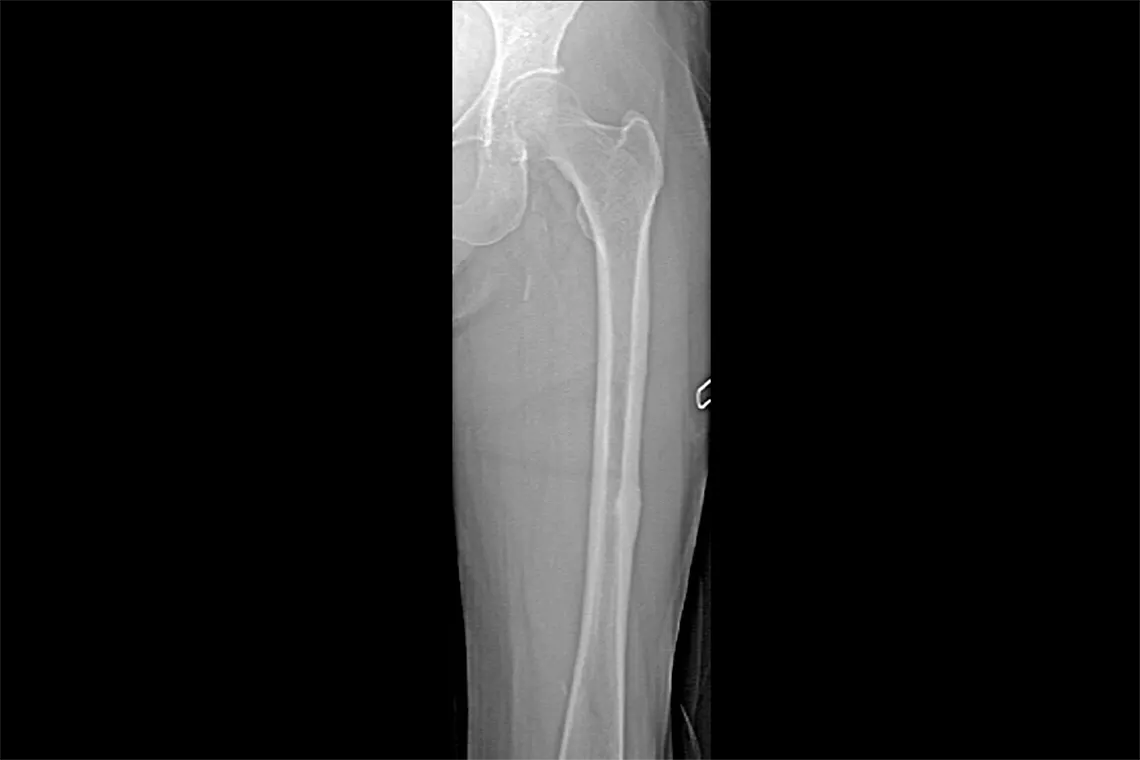

Horizon DXA produit des images de qualité radiographique de l’ensemble du fémur pour l’évaluation des éventuelles fractures atypiques du fémur.31 Une acquisition rapide de 15 secondes révèle l’épaississement du cortex de l’os, ce qui permet de surveiller rapidement et facilement les effets d’un traitement aux bisphosphonates au fil du temps.